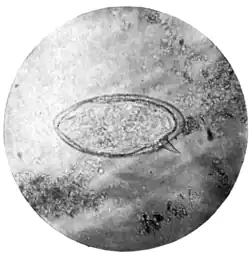

| Fig. 1.—Terminal-spined egg of Schistosomum hæmatobium. (Microphotograph: Dr. Bell.) |

Fig. 2.—Lateral-spined egg of Schistosomum mansoni. (Microphotograph: Dr. Kerr.) |